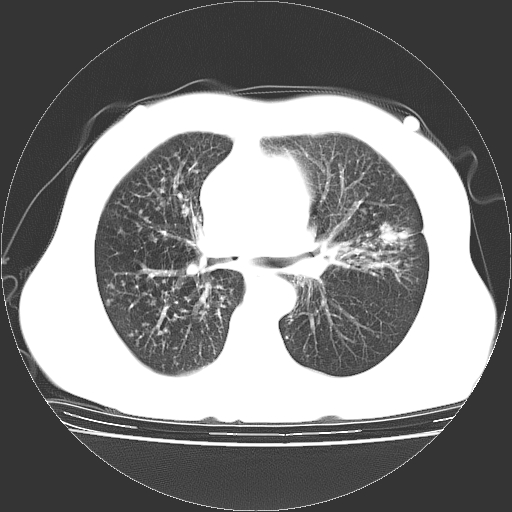

标题: CT23067:女,70岁,咳嗽、咳痰一个月,低热一周。 [打印本页]

女,70岁,咳嗽、咳痰一个月,低热一周。

1.左上肺结核,部分纤维化。右肺中下叶部分肺不张,内见液化、坏死及点状钙化,右中下叶支气管壁增厚、管腔狭窄,见多个点状钙化,结合临床考虑支气管内膜结核,建议痰检查抗酸杆菌并参考血沉。两肺多个小圆点状高密度灶,境界模糊,多考虑结核肺内播散。但本人年龄较大首先应支气管镜检以除外右肺癌。

3、两肺肺结核(右肺下叶背段及左肺)。